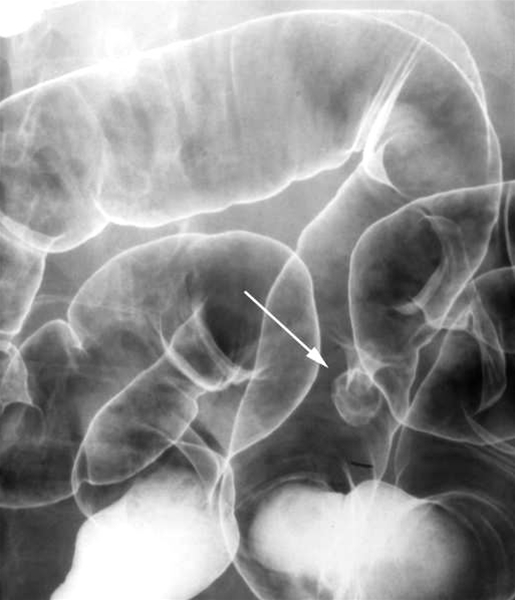

Dobbeltkontrast-røntgenbillede som viser en ca. 15 mm stor stilket polyp (pil) i midterste del af sigmoideum. Idag anvendes koloskopi eller kolegrafi til at påvise polypper.